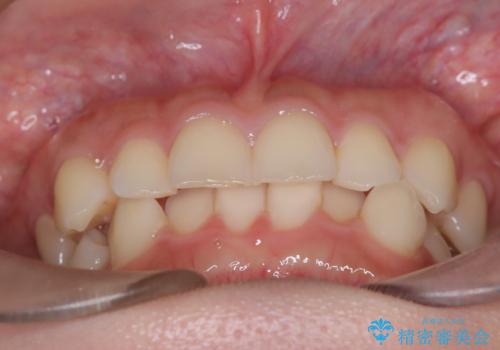

- 前歯のガタガタが気になるとのことでご相談いただきました。診察すると、歯列のスペースが不足し、前歯が重なっている状態でした。抜歯をせずに整えるため、歯と歯の間をわずかに削るIPR(歯列幅径削除)と、奥歯を後方へ動かす遠心移動を組み合わせてスペースを確保しながら並べる治療計画を立てました。

インビザラインを用いて歯を少しずつ移動させながら、IPRで微調整を行い、スペースを確保しました。また、奥歯を遠心移動させることで、前歯を自然な位置に並べることができました。治療後は、「ガタガタがなくなり、スムーズな歯並びになった」と患者様にもご満足いただきました。